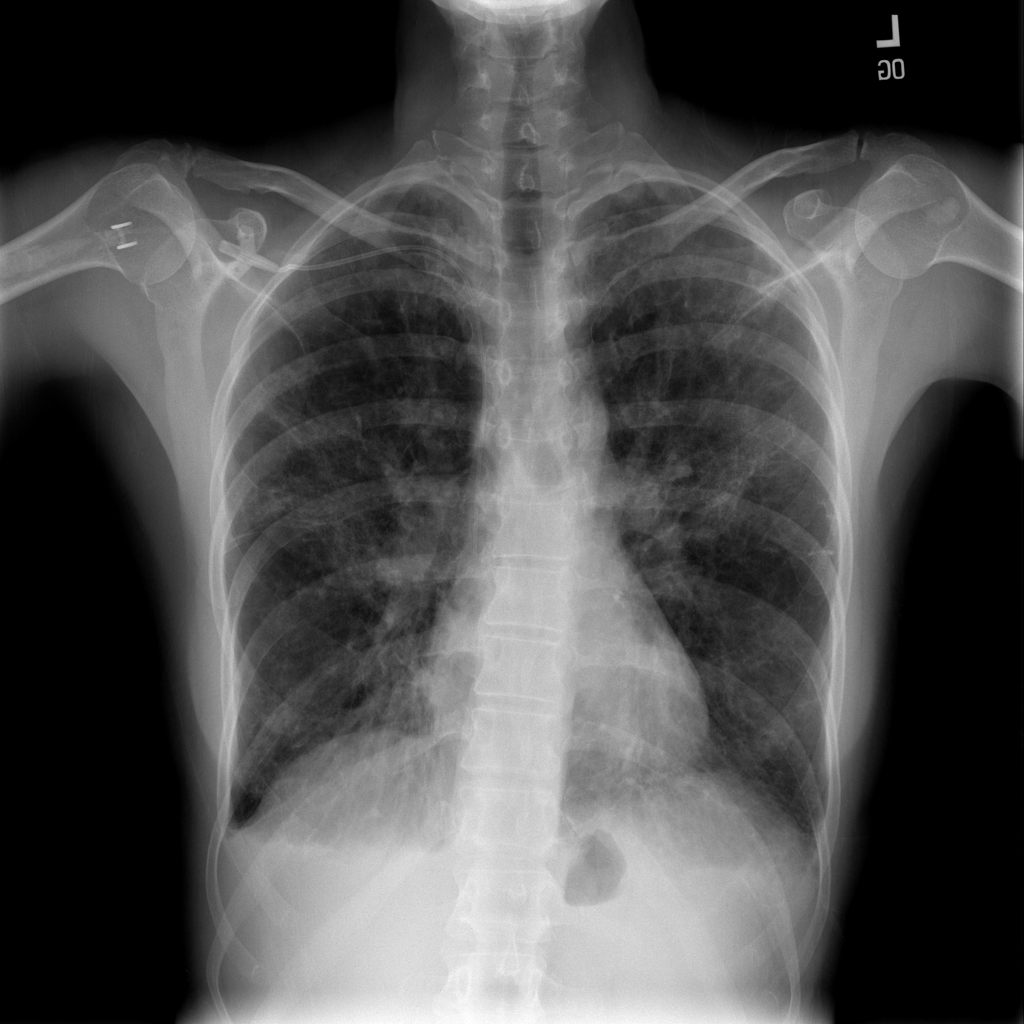

PAT-1F50 · IMG-000Fibrosis

PAT-1F50 · IMG-000

PA